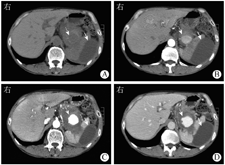

2019年8月7日入院体格检查示体温为36.5 ℃,脉率为78次/min,呼吸频率为20次/min,血压为120/80 mmHg(1 mmHg=0.133 kPa),精神尚可,可自行步入病房,神志清楚,无贫血貌,皮肤、巩膜轻度黄染,浅表淋巴结无肿大,心肺未见明显异常;腹平软,未见胃肠型和蠕动波,未见腹壁静脉曲张,中上腹轻压痛,无反跳痛,未扪及包块,肝脾肋下未扪及,墨菲征阴性,腹部叩诊鼓音,肝肾区无叩击痛,移动性浊音阴性,肠鸣音为4次/min,双下肢无水肿。血常规检查示白细胞计数为3.7×109/L,中性粒细胞占比为0.495,血红蛋白为101 g/L,血细胞比容为31.20%,血小板计数为336×109/L、超敏C反应蛋白为3.89 mg/L;血清淀粉酶为214 U/L。尿常规、粪常规+粪便隐血试验、肝肾功能、血清电解质、凝血功能、肿瘤标志物、甲状腺功能、自身抗体系列、免疫球蛋白G4、人类免疫缺陷病毒、梅毒螺旋体抗体均阴性。2019年8月7日上腹部CT增强扫描检查(图1、图2)提示慢性胰腺炎急性发作、胰腺多发结石,胰体尾部巨大假性囊肿,假性囊肿内脾动脉假性动脉瘤可能,脾囊肿。2019年8月8日磁共振胰胆管造影(magnetic resonance cholangiopancreatography,MRCP)示左右肝管、肝总管、胆总管粗细不均,局部显示不清,但未见扩张,其内未见明显充盈缺损,胰腺体尾部和脾门区见一长径约10 cm的类长圆形异常信号影,T1、T2加权像均呈混杂信号。脾脏外侧及其后方见一囊状水样信号,长径约7 cm。2020年10月13日入院体格检查示腹部有一长约10 cm手术切口,左侧脾窝穿刺引流管在位,引流液较少,腹软,腹部无压痛和反跳痛。血常规检查示白细胞计数为6.8×109/L,血清淀粉酶为196 U/L。假性囊肿引流液李凡他试验弱阳性,乳糜试验阳性,淀粉酶>12 000 U/L。上腹部CT增强扫描检查示慢性胰腺炎腹部术后,术区及其周围改变。

于2019年8月7日急诊行腹腔动脉造影+脾动脉瘤栓塞术(图3),术中经右侧股动脉穿刺置管后,引入5 F Corba导管行腹腔干造影,见脾动脉一条分支中段造影剂外漏,形成假性动脉瘤。经微导管超选择脾动脉出血分支,于破口远端和近端分别予6 mm×2 mm弹簧圈各2枚栓塞,复查造影栓塞满意。最后经Corba导管行腹腔干造影未见明显造影剂外渗,弹簧圈均在位。术后静脉滴注奥美拉唑40 mg(1次/d)抑酸护胃,加贝酯300 mg(1次/d)静脉滴注抑制胰酶活性。患者全身营养状况显著改善后,于2020年10月13日行全身麻醉下胰管切开取石+胰管-空肠吻合+广泛肠粘连松解术,术中见胰腺组织明显萎缩,质地硬,胰尾和脾周致密粘连,胰体尾部假性囊肿与周围组织紧密粘连难以剥离,且易出血。于胰腺表面纵行切开至胰管,沿主胰管纵行切开约5 cm,取出其内结石。取距离十二指肠悬韧带远端约25 cm处空肠,经结肠后方,以可吸收缝线行胰管-空肠侧侧吻合。取距离胰肠吻合口远端约50 cm处空肠,与胰肠吻合口近端空肠行空肠-空肠侧侧吻合。丝线扎闭胰肠吻合口近端肠段,完成非离断式(uncut) Roux-en-Y吻合。2020年10月16日上腹部CT平扫加增强扫描检查(图4)可见胰腺头颈部和部分体部多发点状高密度影,胰腺尾部可见金属伪影,增强扫描无明显强化,周围见部分渗出。术后予以醋酸奥曲肽注射液抑制胰腺分泌,并行窦道造影后以0.9%氯化钠溶液反复冲洗引流管,2周后患者引流液明显减少,无发热、畏寒等不适,予以出院。患者出院后定期复查,胰腺假性囊肿持续置管引流,每日引流约20 mL淡黄色透明液体。2021年3月28日起患者胰腺假性囊肿引流液呈乳糜样(图5),每日引流量为20~30 mL,无畏寒、发热。